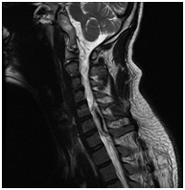

Meningeoma felső nyaki régióban a gerinccsatorna

T2VI T1 (kontraszt)